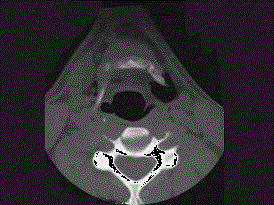

问题 27岁男性,开车外出在高速行驶时翻车,呼吸困难,喉部肿胀,CT检查如图所示,请选择正确的描述或诊断 ( )

选项 A、左侧杓状软骨骨折 B、考虑喉、气管破裂 C、左侧梨状窝软组织肿胀 D、颈部、胸骨下方软组织积气 E、左侧甲状软骨骨折

答案 BCDE